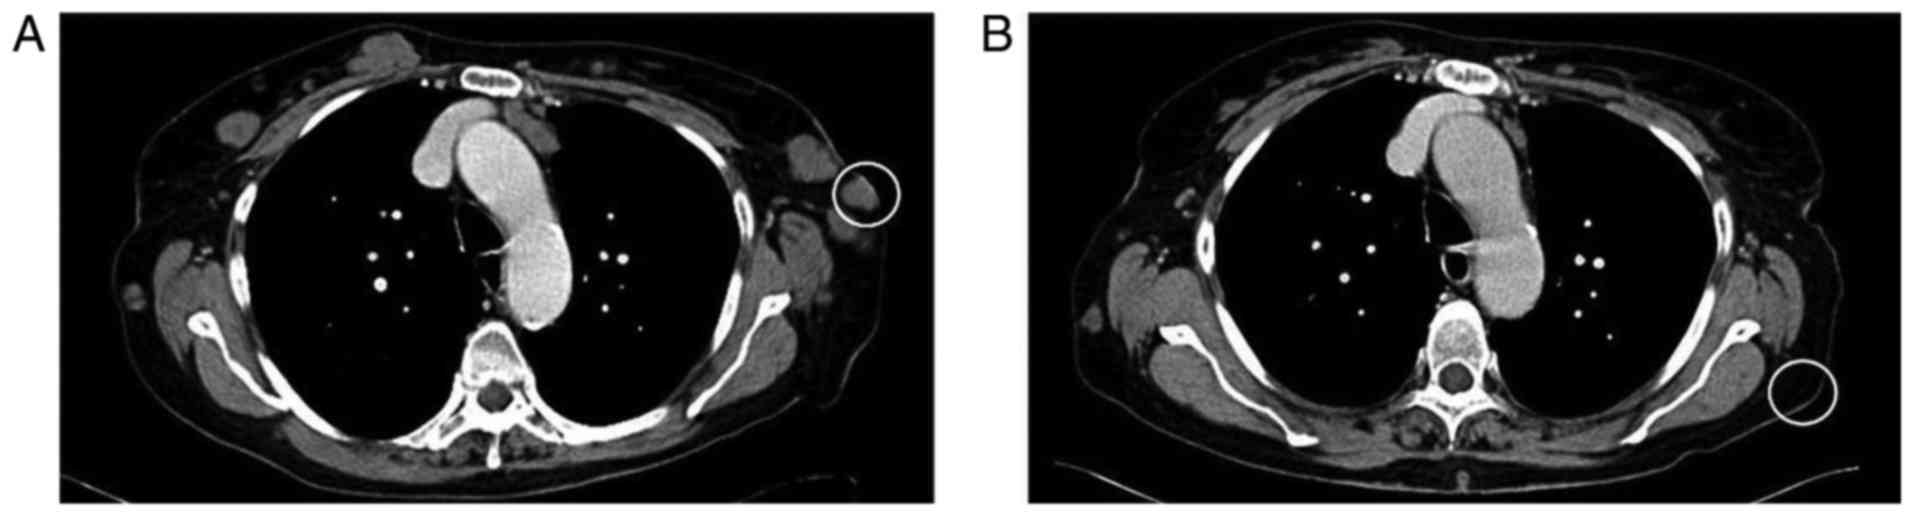

Figure 1